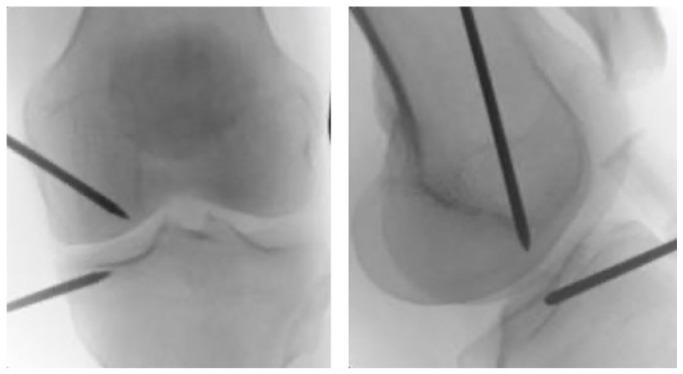

Knee osteoarthritis is a degenerative condition characterized by progressive cartilage degradation, subchondral damage, and bone remodelling. Among the approaches implemented to achieve symptomatic and functional improvements, injection treatments have gained increasing attention due to the possibility of intra-articular delivery with reduced side effects compared to systemic therapies.In addition to well-established treatment options such as hyaluronic acid (HA), cortico-steroids (CS) and oxygen-ozone therapy, many other promising products have been employed in the last decades such as polydeoxyribonucleotide (PDRN) and biologic agents such as platelet-rich plasma (PRP) and mesenchymal stem cells (MSCs). Moreover, ultrasound-guided intra-meniscal injection and X-ray-guided subchondral injection techniques have been introduced into clinical practice.Even when not supported by high evidence consensus, intra-articular CS and HA injections have gained precise indications for symptomatic relief and clinical improvement in OA. Biological products are strongly supported by in vitro evidence but there is still a lack of robust clinical evidence. PRP and MSCs seem to relieve OA symptoms through a regulation of the joint homeostasis, even if their capability to restore articular cartilage is still to be proved in vivo.Due to increasing interest in the subchondral bone pathology, subchondral injections have been developed with promising results in delaying joint replacement. Nevertheless, due to their recent development and the heterogeneity of the injected products (biologic agents or calcium phosphate), this approach still lacks strong enough evidence to be fully endorsed.Combined biological treatments, nano-molecular approaches, monoclonal antibodies and 'personalized' target therapies are currently under development or under investigation with the aim of expanding our armamentarium against knee OA. Cite this article: 2021;6:501-509. DOI: 10.1302/2058-5241.6.210026.

膝关节骨关节炎是一种退行性疾病,其特征为软骨进行性退化、软骨下损伤和骨重塑。在为实现症状缓解和功能改善而采用的各种方法中,注射治疗因其相较于全身治疗具有关节内给药且副作用较小的可能性而受到越来越多的关注。除了透明质酸(HA)、皮质类固醇(CS)和氧-臭氧疗法等成熟的治疗选择外,在过去几十年中还应用了许多其他有前景的产品,如聚脱氧核糖核苷酸(PDRN)以及生物制剂,如富血小板血浆(PRP)和间充质干细胞(MSC)。此外,超声引导下半月板内注射和X线引导下软骨下注射技术已引入临床实践。即使缺乏高证据共识的支持,关节内注射CS和HA在OA的症状缓解和临床改善方面也已获得明确的适应证。生物制品得到了体外证据的有力支持,但仍缺乏强有力的临床证据。PRP和MSC似乎通过调节关节内环境稳定来缓解OA症状,尽管它们恢复关节软骨的能力仍有待在体内得到证实。由于对软骨下骨病理学的兴趣日益增加,已开发出软骨下注射技术,在延迟关节置换方面取得了有前景的结果。然而,由于其发展时间较短且注射产品(生物制剂或磷酸钙)具有异质性,这种方法仍缺乏足够有力的证据来获得充分认可。联合生物治疗、纳米分子方法、单克隆抗体和“个性化”靶向治疗目前正在研发或研究中,旨在扩充我们对抗膝关节OA的手段。引用本文:2021;6:501 - 509。DOI:10.1302/2058 - 5241.6.210026。